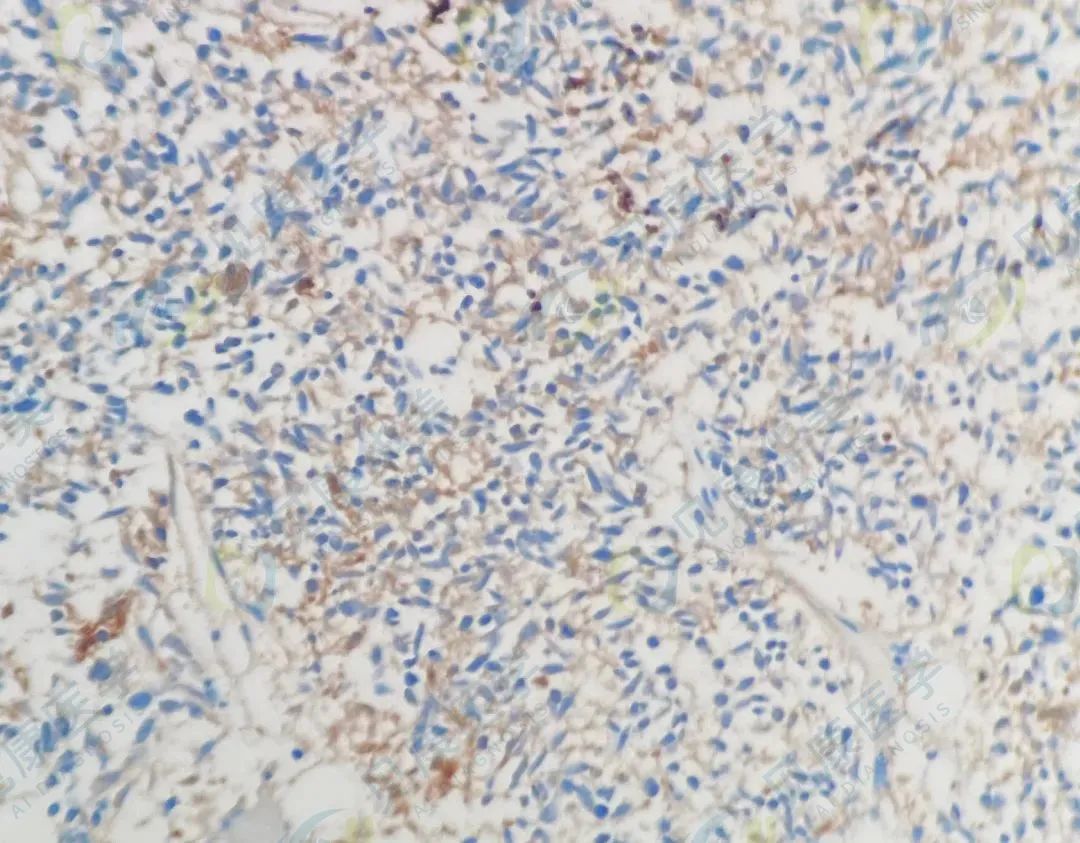

CK(阳性)

CAM5.2(阳性)